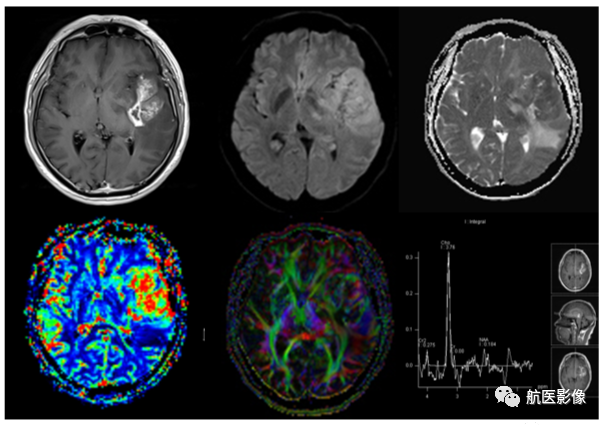

7.脑肿瘤MR多模态检查:

可以在术前对脑肿瘤的良恶性、侵袭范围及相关分子生物学特征做出更准确的判断,为临床确定治疗方案、手术方法、评估预后和临床治疗目标提供影像学依据。